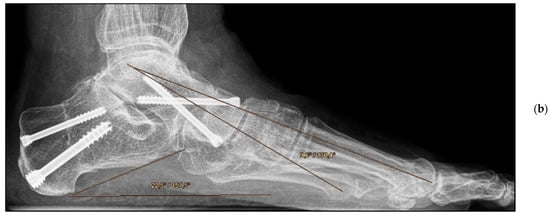

Figure 4.

Pre- and post-operative radiographic findings of double arthrodesis, left foot. (a) Anteroposterior view pre-operative, (b) anteroposterior view post-operative.

Figure 5.

Pre- and post-operative radiographic findings of double arthrodesis, left foot. (a) Lateral view pre-operative, (b) lateral view post-operative after implant removal.